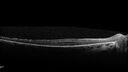

23 year old female Extended HPI: Vision trouble for about five years. She has some trouble with night vision and was told that her retina looked abnormal. There are no family members that are known to have an inherited retinal disease. Medical Hx: Sensorial Neural Hearing Loss. Chorionic migranes. Systemic Meds: None. VA 20/32 OD, 20/25 OS Color vision normal Heterozygous for USH2A pathological mutation and for an USH2A VUS

Usher Syndrome - USH2A212 views23 year old female Extended HPI: Vision trouble for about five years. She has some trouble with night vision and was told that her retina looked abnormal. There are no family members that are known to have an inherited retinal disease.

Medical Hx: Sensorial Neural Hearing Loss. Chorionic migranes.

Systemic Meds: None.

VA 20/32 OD, 20/25 OS

Color vision normal

Heterozygous for USH2A pathological mutation and for an USH2A VUS